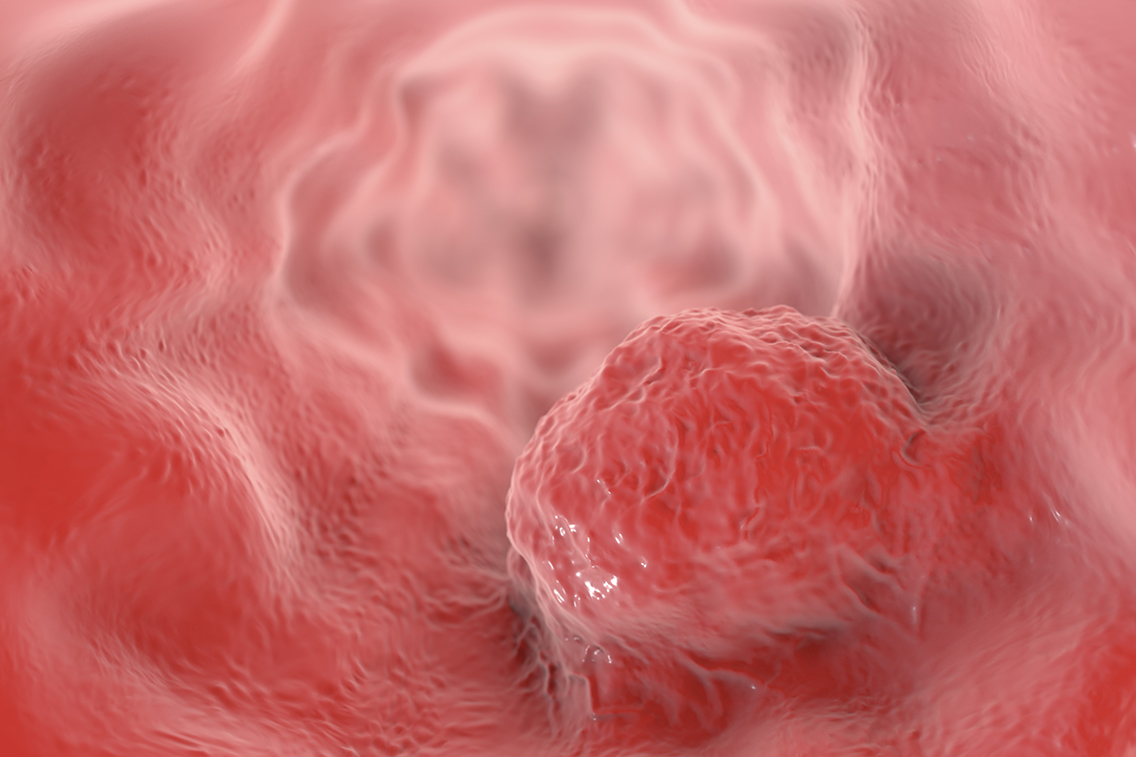

Multilocular cystic renal cell carcinoma (MCRCC)